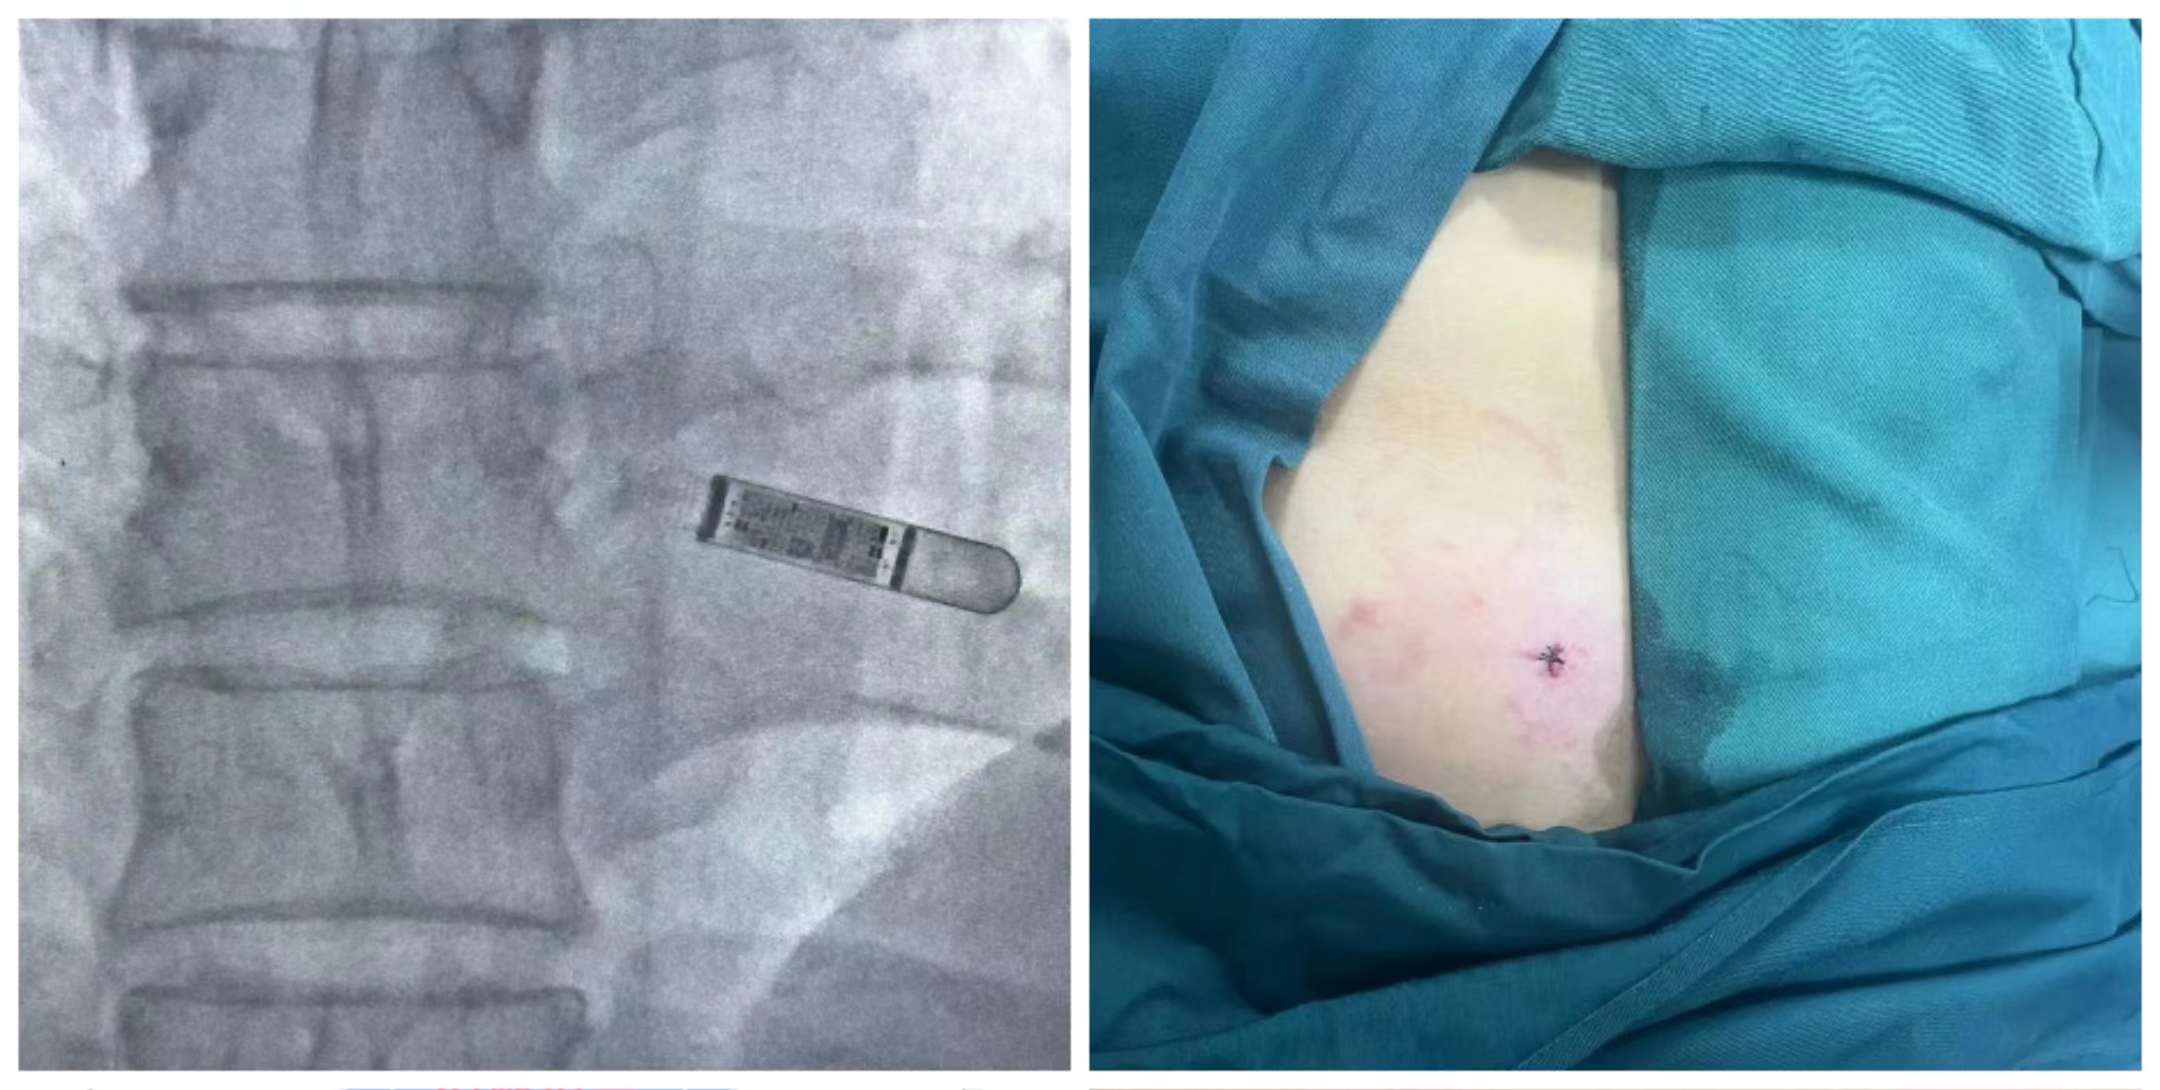

2023年9月1日,慶陽市人民醫(yī)院全科醫(yī)學(xué)科成功完成慶陽市首臺“Reveal LINQ”(植入式心電事件記錄器)的植入,標(biāo)志著我院在心血管疾病診療領(lǐng)域又邁出了堅實的一步。

患者為52歲男性,數(shù)年內(nèi)反復(fù)發(fā)生暈厥,各項輔助檢查無異常,動態(tài)心電圖曾捕捉到陣發(fā)性室性心動過速,盡管高度懷疑心源性暈厥,但植入心臟埋藏式轉(zhuǎn)復(fù)除顫器的指征并不強烈,因此考慮為患者植入心電事件記錄器,有效記錄心臟事件,希望能為患者進一步治療提供有效證據(jù)。與患者及家屬充分溝通后,于2023年9月1日行ICM植入術(shù),手術(shù)過程順利,術(shù)中、術(shù)后患者生命體征平穩(wěn),未出現(xiàn)不良反應(yīng)。

2.小巧精細(xì),只有口香糖一半大小,重約2.5g,植入ICM不影響磁共振檢查,可安全接受1.5和3.0 Tesla的磁共振掃描。

3.精巧植入,ICM采用注射方法植入,無需制作囊袋,創(chuàng)傷微小,操作簡單。